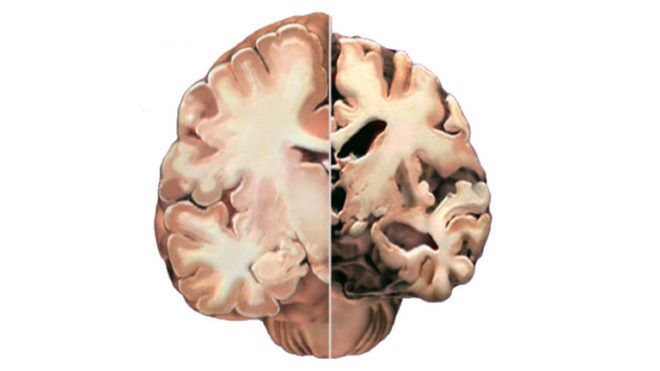

Egészséges és Alzheimer-kór által elsorvasztott agy keresztmetszete (Fotó: Tumblr)